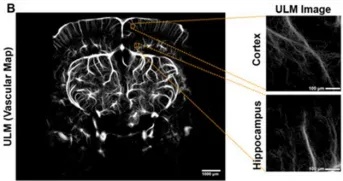

美國俄克拉荷馬大學研究團隊在年輕和老年小鼠上,比較了功能超聲成像(fUS)與激光散斑對比成像(LSCI)對胡須刺激誘發的功能性超灌注的測量結果。兩種方法的一致性極高(Pearson相關系數r=0.92),且隨年齡增加,反應幅度均明顯下降:LSCI由約10% 降至4%,fUS由約15% 降至4%。結果提示功能超聲成像(fUS)不僅是評估功能性超灌注的可靠替代,還因成像深度更大、靈敏度更高而在表層無法覆蓋的腦區具有優勢。研究進一步用ULM繪制微血管密度,并與免疫熒光染色結果對比,相關性良好(r=0.82),為功能超聲成像(fUS)在老齡相關血管功能障礙與神經退行性疾病研究中的應用提供了有力證據。

圖4 上:利用功能超聲(fUS)獲取的小鼠大腦額面和矢狀面圖像,展示了在動物安裝顱窗 14 天后,對胡須刺激所產生的功能性充血反應的比較。可以明顯看到,(上方)年輕動物與(下方)老齡動物之間反應的下降。右:代表性的超聲定位顯微(ULM)血管圖,以及用于與激光散斑對比成像(LSCI)進行比較的代表性 500 µm² 取樣區域。